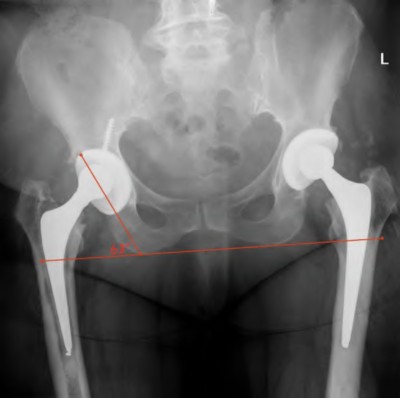

When planning a primary THA, the surgeon uses the AP pelvis radiograph to assess leg length discrepancy.

Which of the following radiographic landmarks is most reliable for establishing a horizontal reference line for leg length measurement?